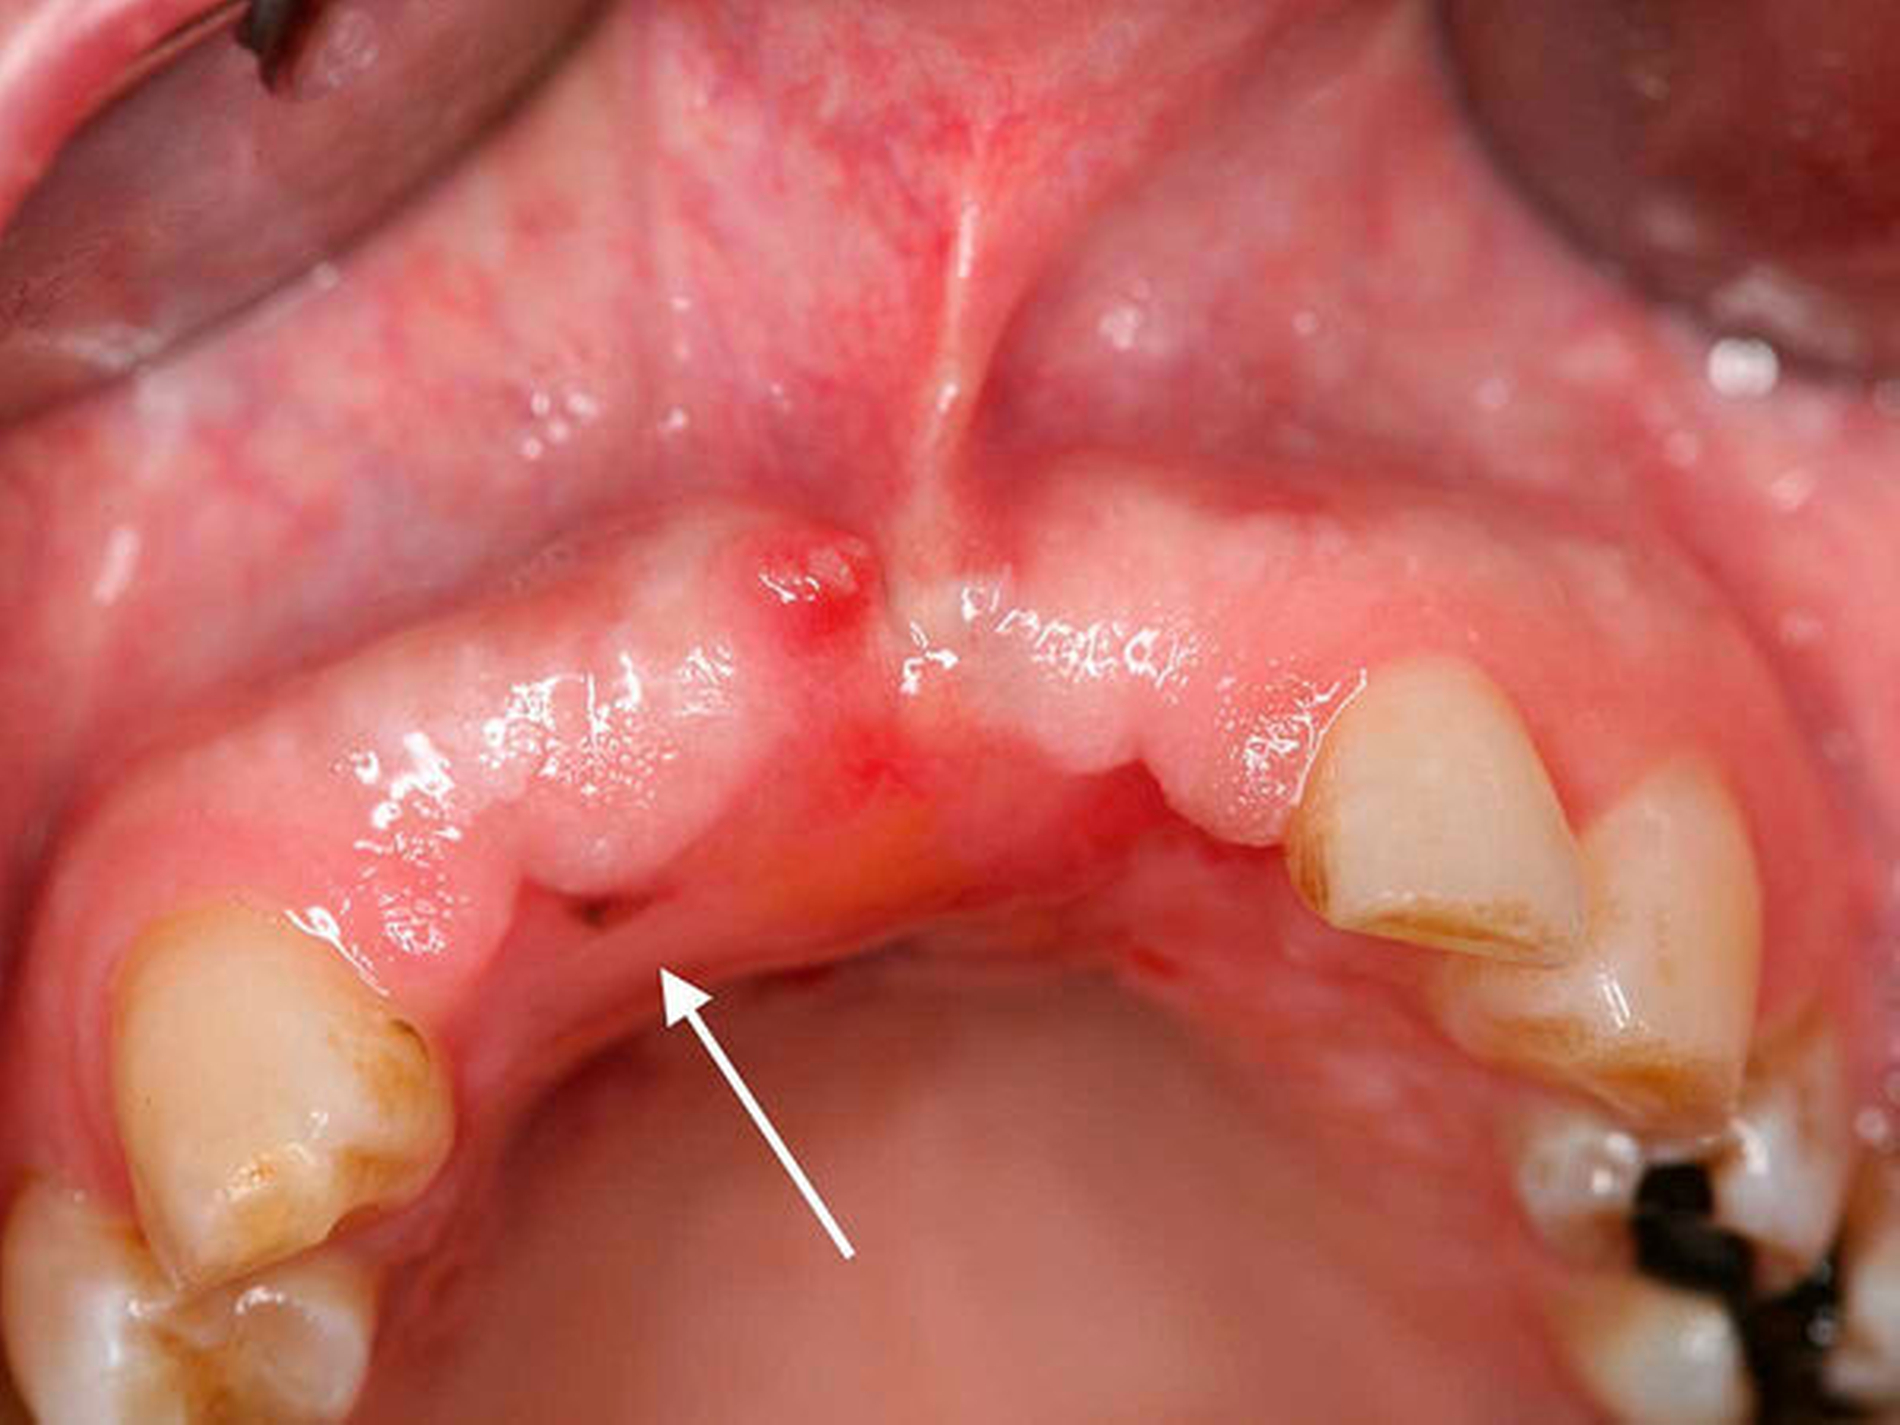

Anschließend wurde zur Ausbreitungsdiagnostik eine Magnetresonanztomografie (MRT) der Kopf-Hals-Weichteile mit Kontrastmittel durchgeführt (Abbildung 2). Hierbei kam eine malignomsuspekte Raumforderung im Oberkiefer im Bereich der regiones 11 bis 21 zur Darstellung, metastasensuspekte Auffälligkeiten der Halslymphknoten konnten nicht ausgemacht werden. Nach Besprechung des Falles in der interdisziplinären Tumorkonferenz wurde der Befund lokal mit Sicherheitsabstand in toto exzidiert und die mit der Raumforderung kommunizierenden Zähne 12, 11 und 21 extrahiert (Abbildung 3).

Nach drei Monaten war erneut eine circa 2 mm x 2 mm große schwärzliche Mundschleimhautveränderung in regio 012 auffällig (Abbildung 4). Die Raumforderung inklusive einer kortikalen Knochenspange des Alveolarkamms und des Os palatinum von regio 13 bis regio 23 wurde großflächig reseziert. Histopathologisch wurde ein R0-reseziertes Rezidiv des vorbekannten Melanoma in situ bestätigt, eine tiefere Tumorinfiltration über die Basalmembran hinweg oder sogar bis in den ortsständigen Knochen konnte ausgeschlossen werden.